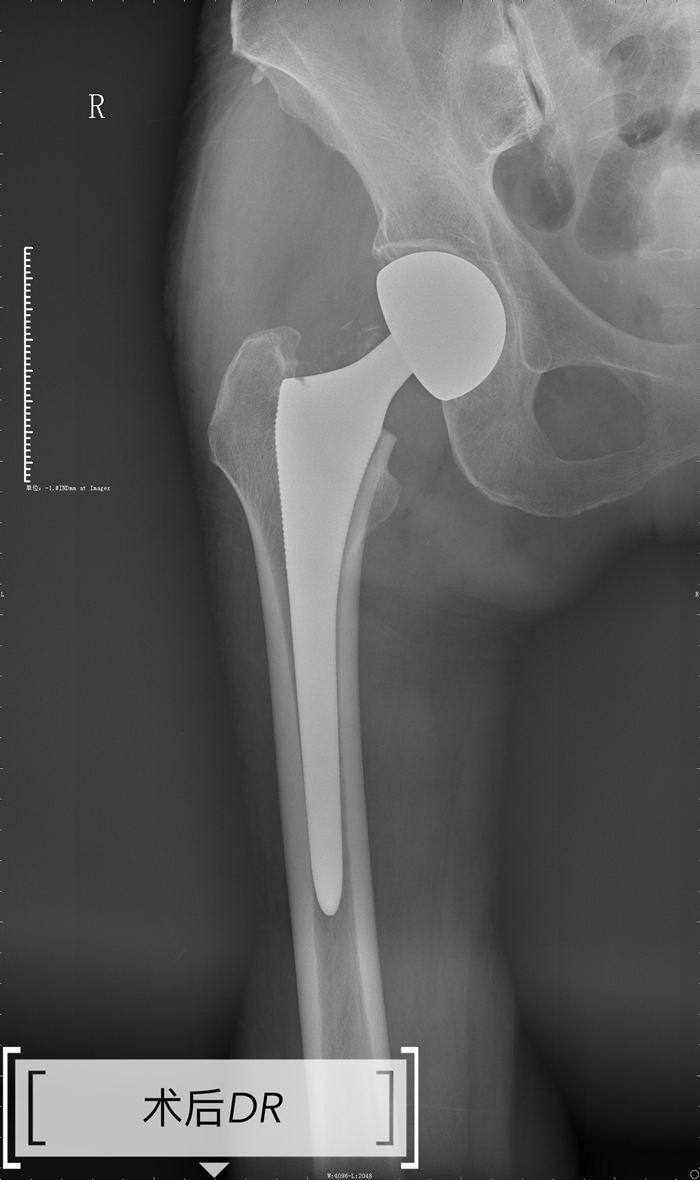

据悉,该名78岁的高龄患者因摔伤致右股骨颈骨折遂到我院就诊,骨伤科手术团队为其制定了详细的诊疗方案,考虑患者年龄较大,訾主任秉持微创化操作技术理念,决定为患者行右人工股骨头置换术,术中运用改良后外侧入路,最大限度保护髋短外旋肌群,把软组织的损伤降到最低,控制缩短手术时间和减少术中出血,患者术后恢复非常满意。患者术后一小时即下床负重站立,搀扶行走,术后第二天即可下床扶助行器行走,对此疗效,患者和家属非常满意,喜笑颜开。(通讯员/骨伤科 罗健飞)

人工髋关节置换术是治疗股骨颈骨折、髋关节坏死及终末期髋关节炎的有效方法,这一治疗方法在我国已得到广泛应用,但是骨科手术患者通常要承受较严重的创伤及痛苦,同时患者自身机体系统并发症和合并症较多。近年来加速康复外科理念被逐渐运用在骨科手术患者围手术期管理上,取得满意效果。